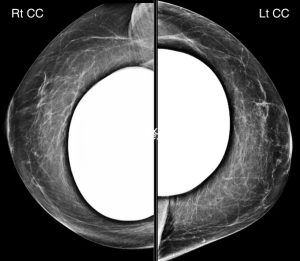

There is a unilateral finding present. What is it?

C. Left breast lower outer quadrant fat-containing mass

Explanation: The fat-containing mass shown below is present in the lower outer quadrant of the left breast.

Mammography is not a sensitive modality to assess for silicone implant rupture, although there is no gross evidence of extracapsular silicone implant rupture on these images. Saline implant rupture is a clinical diagnosis.